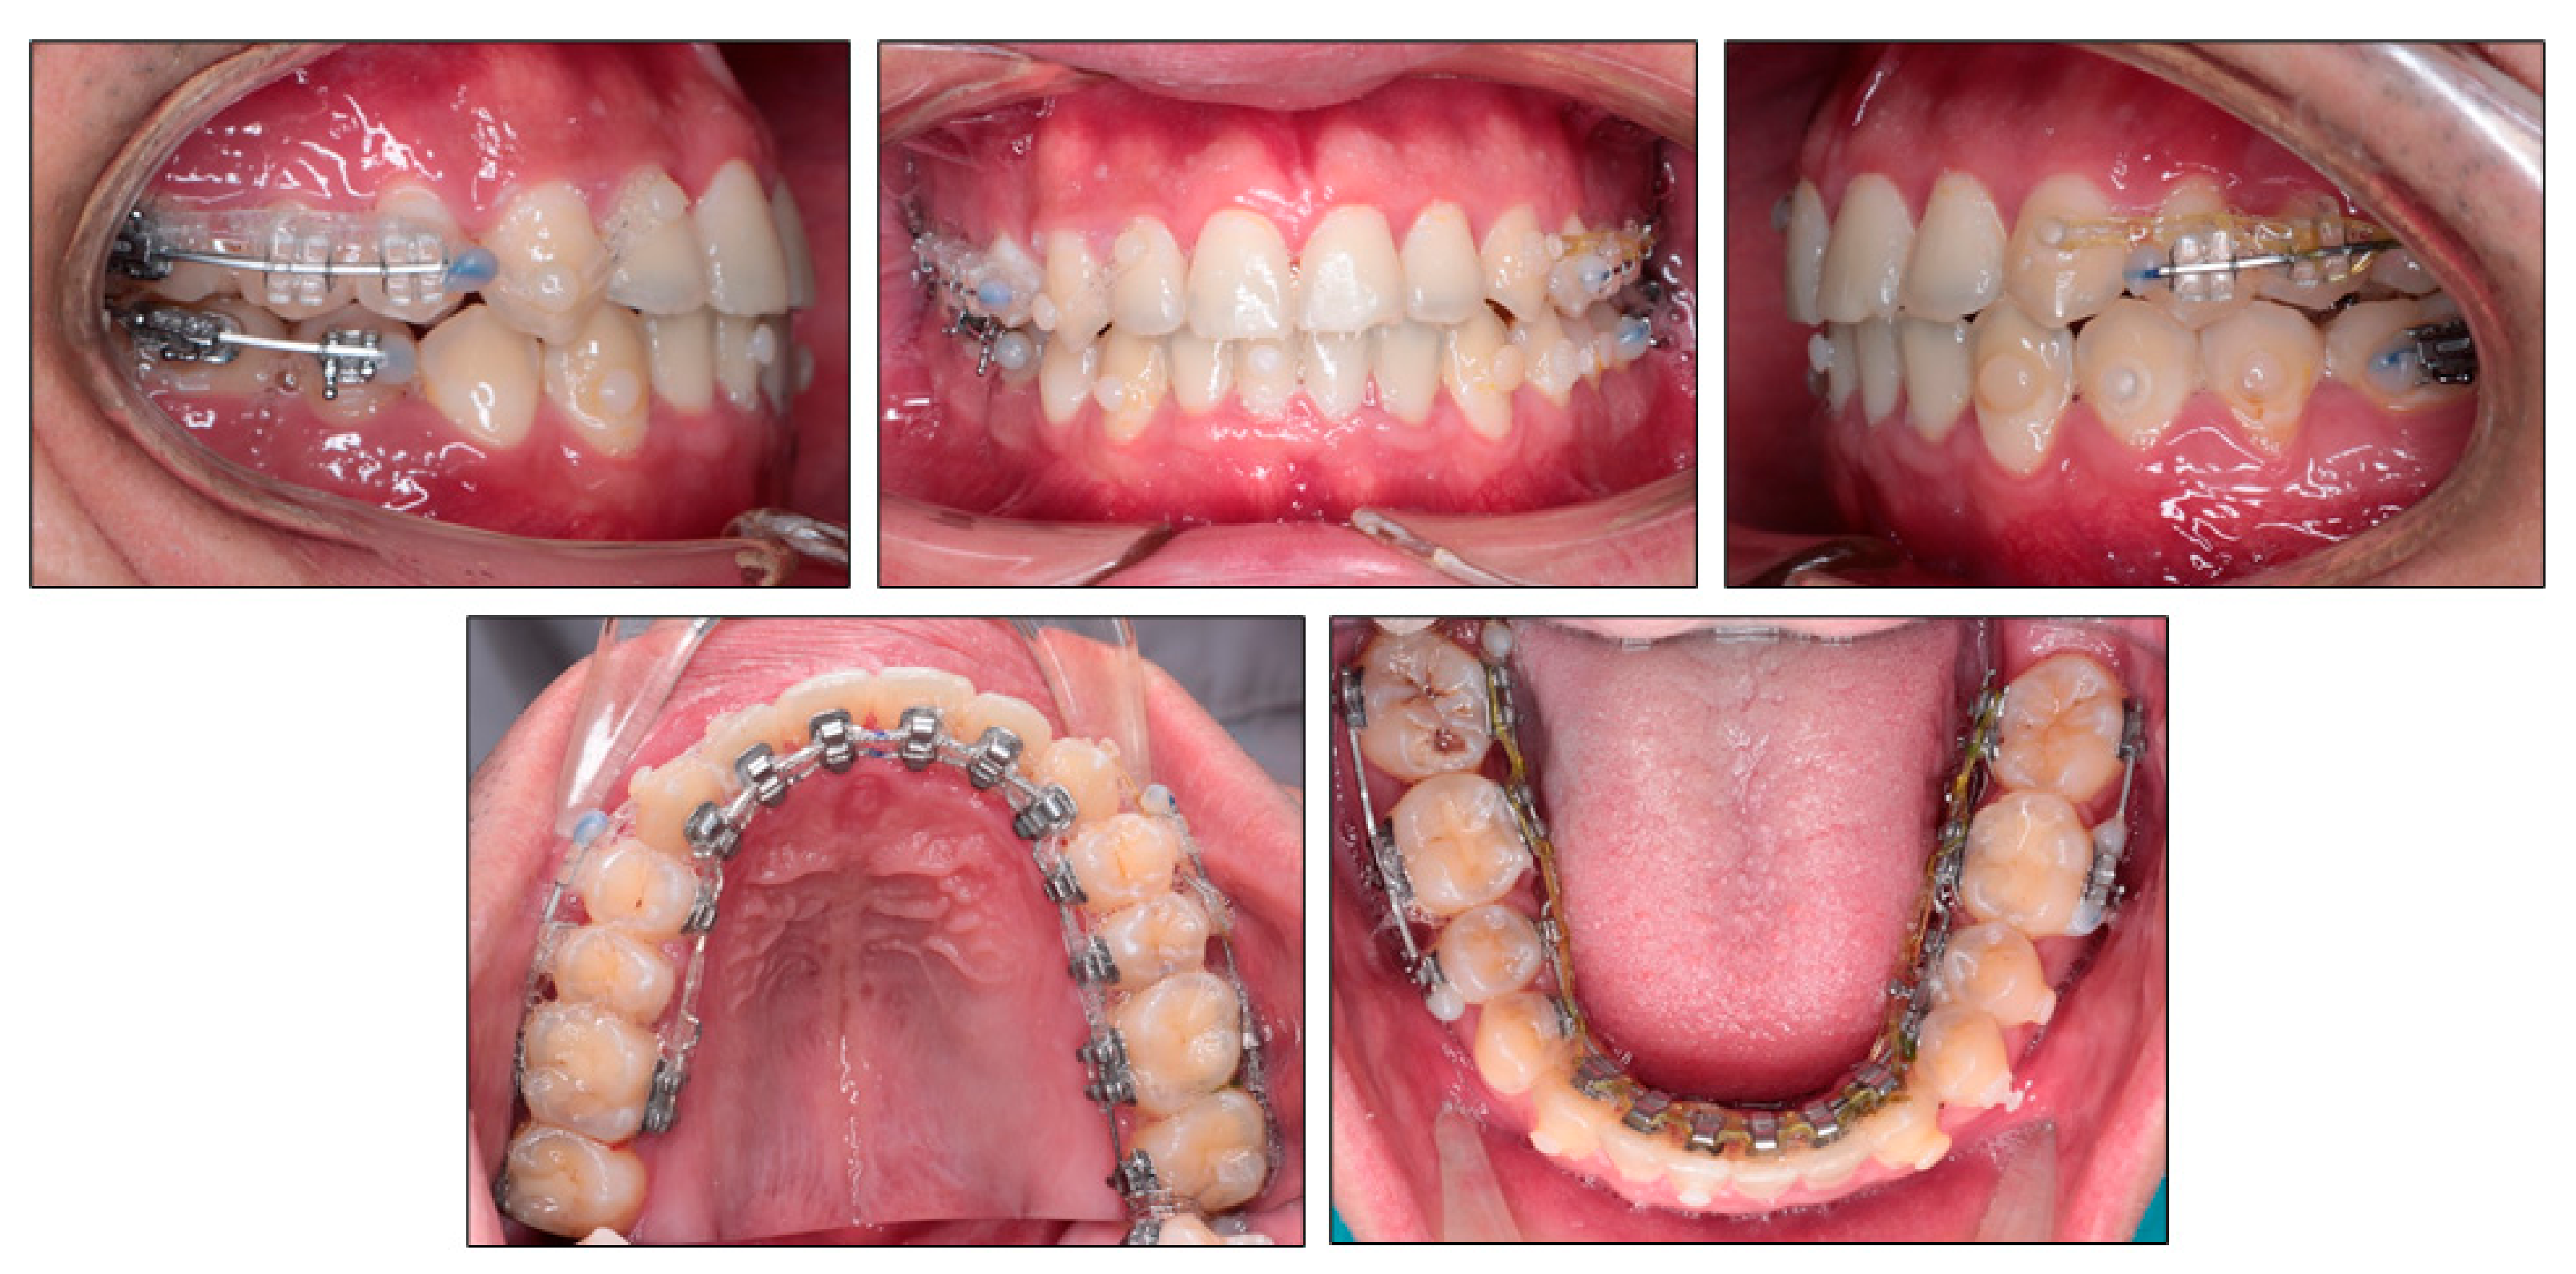

Over the next month, clear brackets (OK resin bracket, Hubit, Anyang-si, Gyeonggi-do, Korea) were bonded to the labial surface of maxillary premolars and segmental archwires were placed from maxillary first premolars to maxillary second molars in order to reinforce the maxillary buccal segment during the wearing of intermaxillary elastics. The cross elastics were applied from the lingual side of maxillary right second premolar to the labial side of mandibular right second premolar and first molar, from the lingual side of mandibular right first molar to the labial side of maxillary right second premolar and first molar and from mandibular left canine to maxillary right canine (Figure 6). Class II elastic was applied on the left side to correct the Class II canine relationship on that side.

Figure 6.

Applying intermaxillary elastics to correct transverse and sagittal discrepancies.